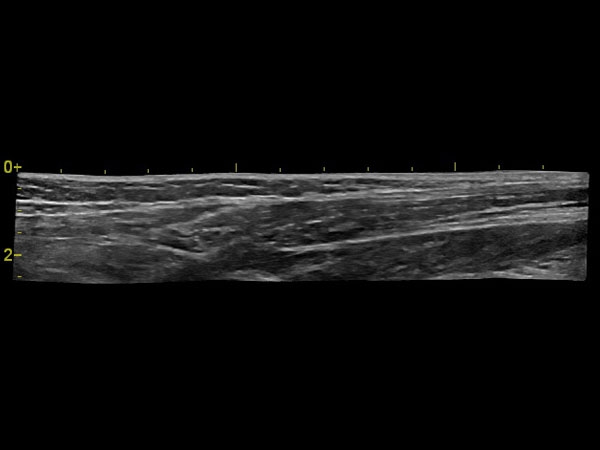

• скелетно-мышечная система;

Да